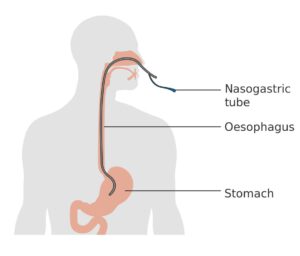

Medical-Surgical Nursing

Cheatsheets

226

Mnemonics

84

Images

318

Picmonic

0